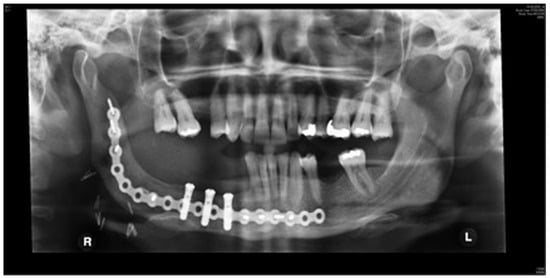

Staged reconstruction was defined as when the reconstruction with the free bone graft was performed as a secondary procedure. This secondary procedure was only performed when the oral mucosa had healed intraorally, sealing the mouth from the defect and the neck. A loadbearing locking mandibular plate was used to maintain the three-dimensional position of the bone and thus the occlusion (see Figure 1, Figure 2, Figure 3, Figure 4, Figure 5, Figure 6, Figure 7, Figure 8, Figure 9, Figure 10 and Figure 11).

Figure 3.

Locking plate to maintain the position of the bony fragments of the mandible while the oral mucosa is healing and margins of the resected pathology awaited.

All the reconstructions in our study were staged. The average length of the free bone grafts was 6.7 cm (range: 6.0–7.1 cm) and the average height of the free bone grafts was 2.3 cm (range: 1.0–3.2 cm). The follow-up period was between 6 and 108 months (average 30 months). Twelve patients had no complications at the recipient site and two patients had minor wound breakdown extraorally, which resolved with antibiotics. One bone graft was lost due to infection. In Birmingham, two patients had been dentally rehabilitated with implants. Another four patients have been scanned and are awaiting dental implant placement. No patient in Florida was dentally rehabilitated with dental implants.

The three-dimensional shape and position of the mandibular fragments was maintained by a strong locking plate, while the oral mucosa healed and the pathology was awaited. The same plate was then subsequently used to secure the free bone graft.

There was no incidence of plate exposure. This technique resulted in a low complication rate. Only one patient had a complication at the recipient site (mandible). The patient had developed a small dehiscence that resolved with a course of antibiotics. Although only two patients of the study group had been dentally rehabilitated, four other patients were awaiting dental implants. Insurance companies in the United States do not fund dental implants and therefore implant-based rehabilitation was rare in Florida. In Birmingham, implant-based rehabilitation is available on the National Health Service, and the unit aims to implant rehabilitate most patients.